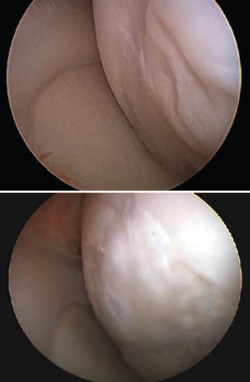

Although there are a number of classifications for assessing the degree of joint cartilage damage, the most widely used option is the classification of Outerbridge (1961), which defines four grades(5,6) (Figure 3):

• Grade I: softening or edema of the cartilage surface.

• Grade II: fissures or fragmentation affecting a surface of less than 1.25 cm in diameter.

• Grade III: fissures or fragmentation affecting a surface of over 1.25 cm in diameter.

• Grade IV: erosion of the cartilage extending to the subchondral bone.

Figure 4 shows arthroscopic images of lesions corresponding to grade II (Figure 4A), grade III (Figure 4B) and grade IV (Figure 4C).